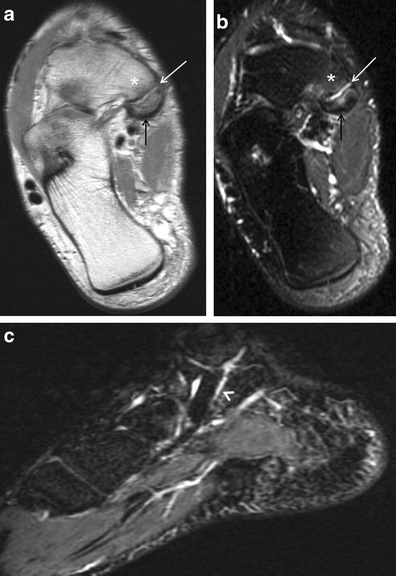

Painful os peroneum syndrome. a Lateral radiograph of the ankle demonstrates the presence of an os peroneum (white arrow). Axial proton density-weighted (b) and T2-weighted fat-saturated (c) MRIs of the ankle show focal tendinosis at the peroneus longus tendon (white arrows) just distal to the os peroneum (black arrow) and surrounding soft tissue oedema (arrowheads). These findings corroborate a painful os peroneum syndrome